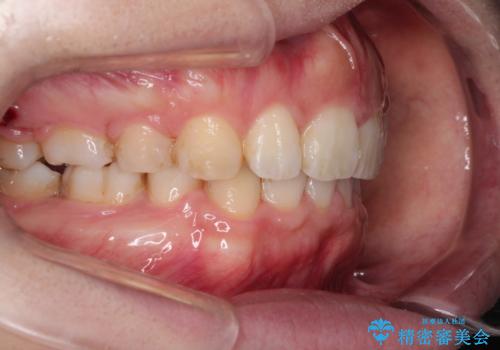

がたがたと出っ歯を直したい ワイヤーによる抜歯矯正

- ガタガタと出っ歯を主訴に来院されました。

上下左右の歯を1本ずつ、合計4本抜歯してワイヤーにて矯正治療をすることとなりました。

前から4番目の歯を抜歯することが多いのですが、右上の前から5番目の歯が神経の治療済みであり、こちらの歯を抜歯する計画としました。

通常より治療期間を要しましたが、健康な歯を残すことができました。